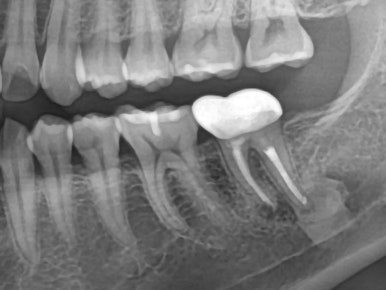

🦷 보철 단계 (3개월 후)

임플란트 식립 후

👉 3개월 동안 골유착을 기다립니다.

이후

✔ ISQ 측정 (고정력 확인)

✔ 맞춤형 지대주 제작

✔ 최종 크라운 장착

✔ 적용된 보철 방식

- Custom Abutment (맞춤 지대주)

→ 음식물 끼임 최소화 - SCRP 크라운

→ 유지보수 용이 + 안정성 확보

🎯 치료 결과 (6개월 후)

✔ 임플란트 안정적 유지

✔ 통증 완전히 해소

✔ 음식물 끼임 없음

✔ 정상적인 식사 가능

👉 환자분 만족도 매우 높은 케이스였습니다 😊